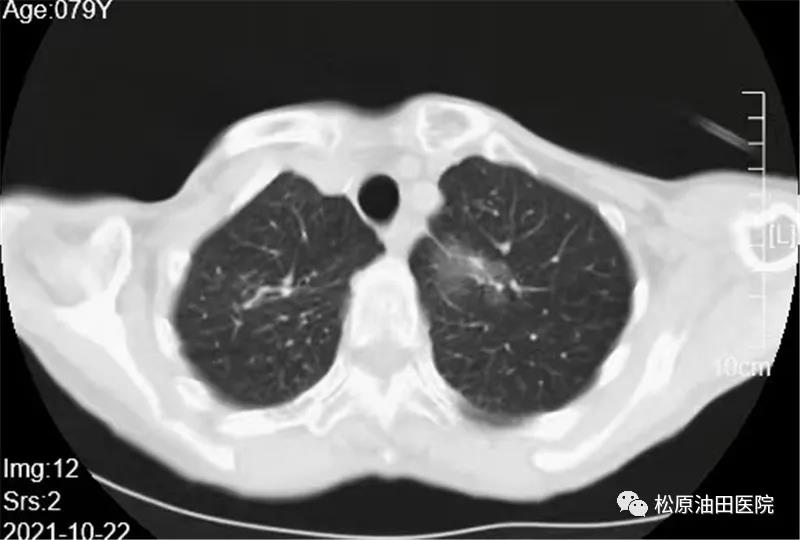

据了解,今年11月4日,赵先生因发烧入院,胸部CT诊断为肺炎及左肺上叶毛玻璃样结节,赵先生和家人都很紧张。经松原吉林油田医院肺结节MDT团队与北京大学肿瘤医院专家柳晨教授联合会诊后,考虑为早期肺癌,决定采用创伤小、术后恢复快、手术费用低的超微创治疗方式——微波消融技术进行手术,3分钟左右即可“烧死”肺部肿瘤。

术前,专家组制定了周密的手术计划,不需要气管插管、下导尿管,手术采用穿刺+微波消融术方式,即取到了病理组织又可以消灭肿物。不到一个小时,消融手术顺利完成。CT扫描显示病灶达到了完全消融,手术宣告成功!术中,赵先生完全处于清醒状态并能正常对话,术后立即能自行行走,并于四天后出院。